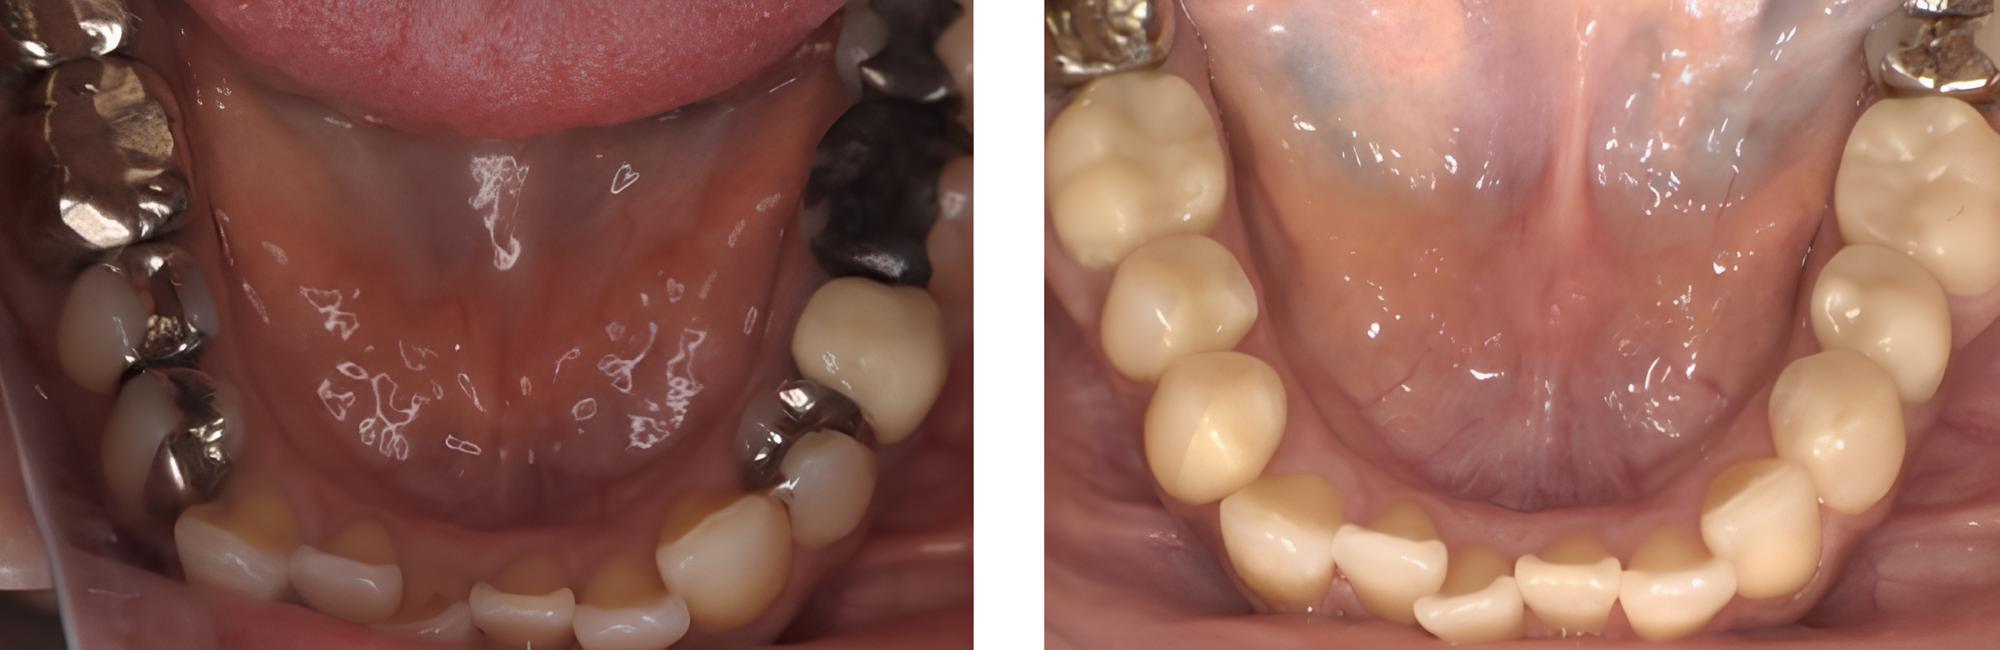

全顎保険治療

術前

術後

| 治療内容 | 全顎的に保険内で治療を行った |

|---|---|

| 治療期間・回数 | 約2.5年・約50回 |

| 費用 | 保険適用となります |

| リスク・副作用 |